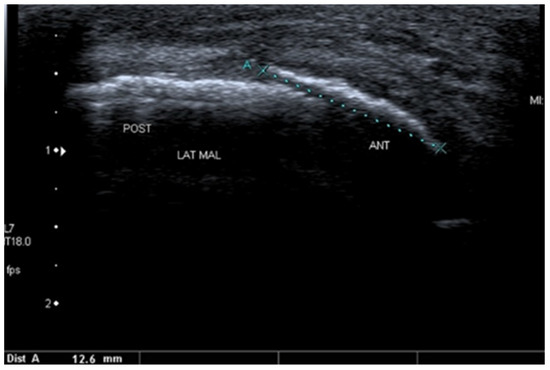

Basic Differences and Most Common Findings in Ultrasound Examinations of Musculoskeletal System in Children: A Narrative Literature Review

by Tomasz Poboży, Wojciech Konarski, Karolina Piotrowska-Lis, Julia Domańska, Kamil Poboży and Maciej Kielar

We present basic differences in the musculoskeletal ultrasound examinations between adults and children. Examiners who deal with adults on a daily basis have shared concerns about examining children. Such concerns may arise from the different approach to child ultrasounds, but they also come [...] Read more.

We present basic differences in the musculoskeletal ultrasound examinations between adults and children. Examiners who deal with adults on a daily basis have shared concerns about examining children. Such concerns may arise from the different approach to child ultrasounds, but they also come from differences in anatomical characteristics according to developmental age. We discuss the presence of growth plates, as well as non-mineralized parts of the bones. We also refer to the pathologies most often found in ultrasounds in early developmental stages. In the PubMed database, the set of keywords: “msk ultrasound in children”, “pediatric msk sonoanatomy”, “coxitis fugax”, “pediatric Baker’s cyst”, “Baker’s cyst ultrasonography”, “bone septic necrosis in ultrasonography”, “ultrasonography in juvenile idiopathic arthritis”, and “ultrasonography in juvenile spondyloarthropathies”, was used to identify a total of 1657 results, from which 54 was selected to be included in the article. We discuss the problem of osteochondritis dissecans, Osgood-Schlatter disease, examples of ligament injuries (especially in relation to the knee and ankle joints), exfoliation of growth cartilages, osteochondroma, exudates and inflammations affecting joints, and Baker’s cysts. In this way, we have collected useful information about the most common diseases of the musculoskeletal system in children. Full article

Show Figures

Figure 1